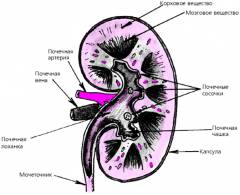

Почки — парные органы бобовидной формы, расположенные по обе стороны от позвоночника. Каждая почка состоит из почечной ткани (паренхимы) и чашечно-лоханочной системы.

Почечная ткань включает корковое вещество с нефронами — функциональными единицами почки, и мозговое вещество с мочевыми канальцами. Здесь образуется моча.

Чашечно-лоханочная система состоит из чашечек и лоханки, где накапливается моча. Каждая почка окружена капсулой.

Анатомия и функции почек

Почка — парный орган в форме боба, расположенный по обе стороны от позвоночника в поясничной области.

В структуре почки выделяют почечную ткань (паренхиму) и систему чашечек и лоханок.

Почечная ткань включает корковое вещество с нефронами — функциональными единицами почки, и мозговое вещество с мочевыми канальцами. В почечной ткани образуется моча.

Система чашечек и лоханок состоит из чашечек и лоханки, где накапливается и выводится моча.

Каждая почка окружена защитной капсулой.